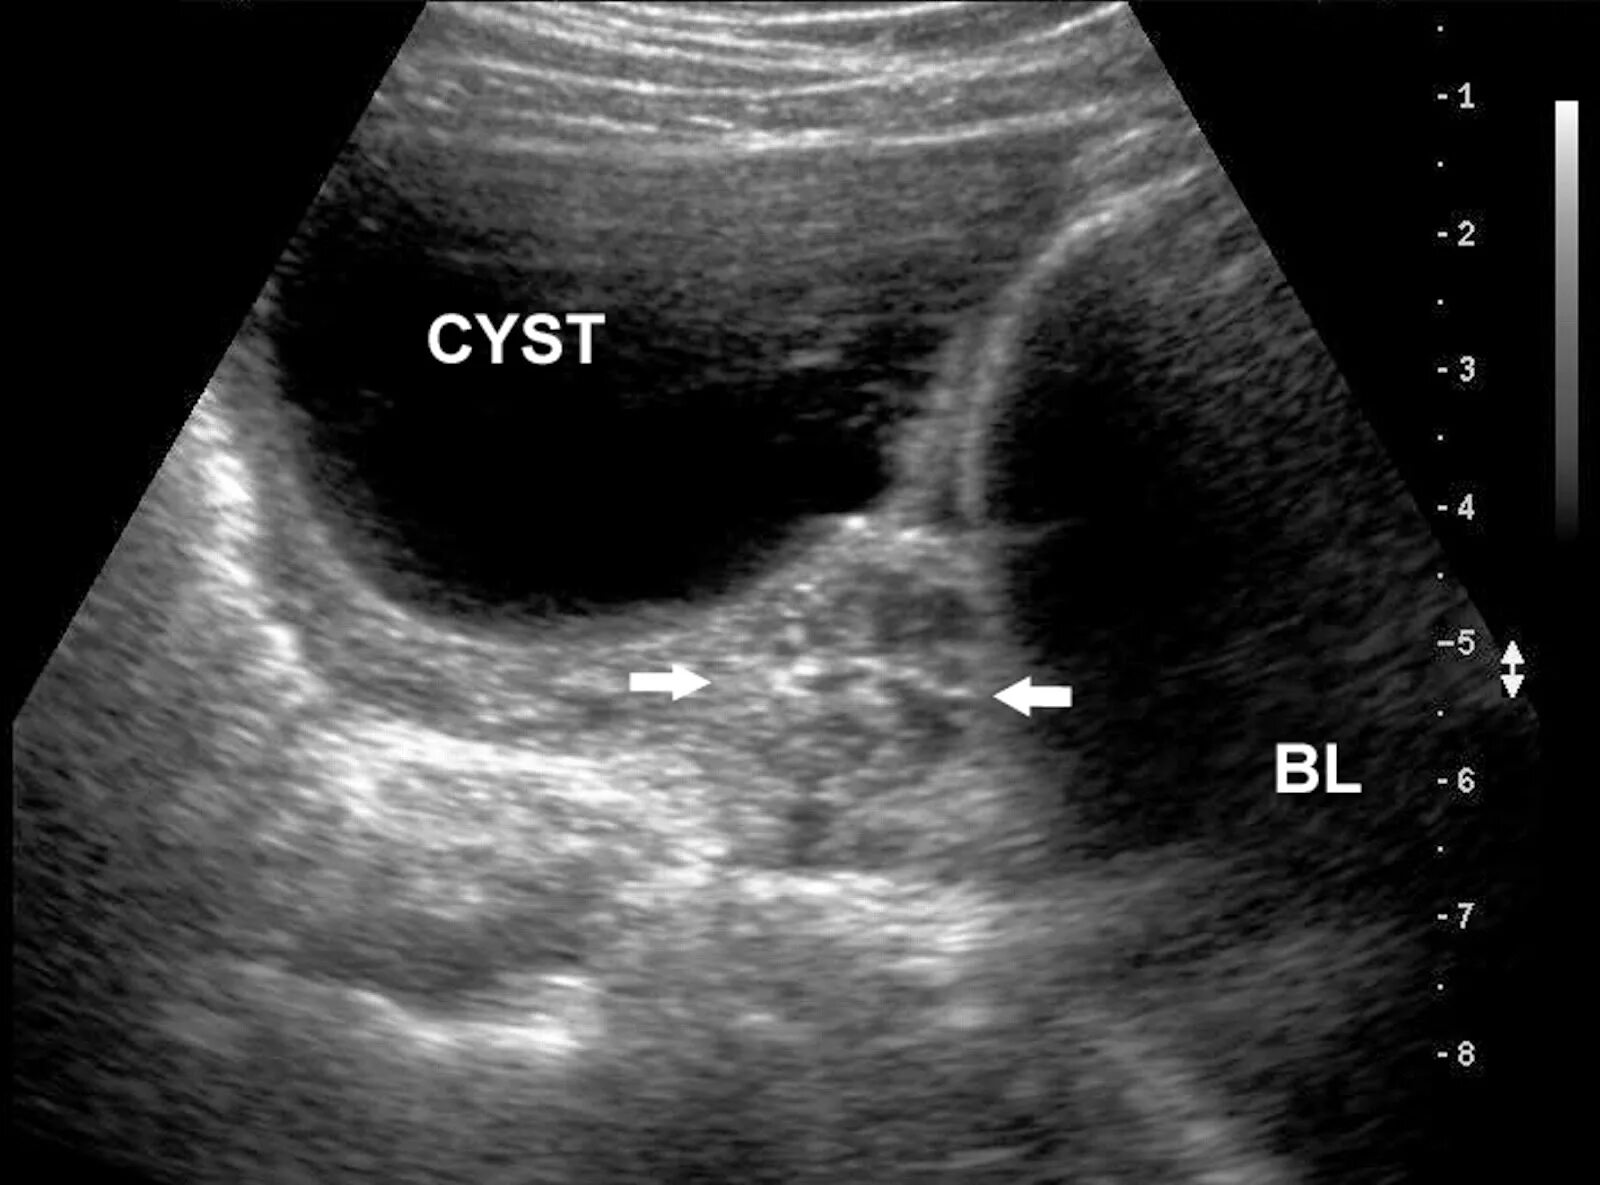

Когда делать узи яичников